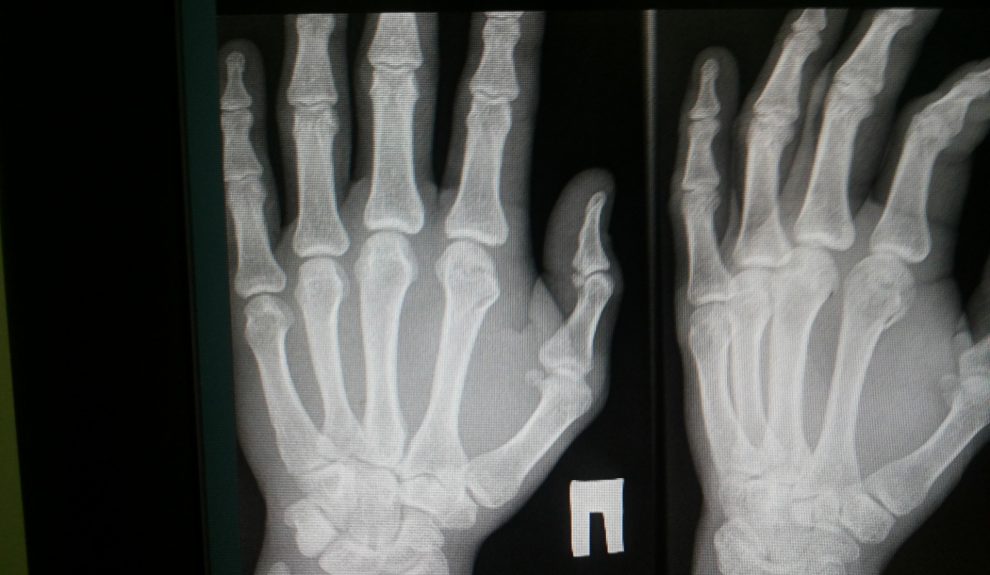

Martín explica que el procedimiento vigente compara la radiografía de la mano izquierda con un atlas estadounidense elaborado con población caucásica de alto nivel socioeconómico en los años 50–70, lo que genera sesgos al aplicarlo a menores subsaharianos. «De una forma práctica, para que se visualice, un niño que tiene 16,5 años puede ser calificado actualmente como de 18 años», afirma, con errores «del orden de dos años» en niñas y «de un año y medio» en niños.

El nuevo método combina tablas de ajuste obtenidas en su investigación con un algoritmo que compara cada radiografía «con una biblioteca de imágenes» construida específicamente por países y etnias de origen. «La inteligencia artificial básicamente compara la radiografía del niño que llega con esas bibliotecas que yo ya previamente había trabajado», señala, subrayando que así la evaluación se hace «con el estándar comparativo de la población de la que proceden estos menores».

Las primeras pruebas muestran mejoras en tiempos y consistencia diagnóstica: el análisis manual de una imagen tarda unos diez minutos y la automatización lo reduce a «solo 15 segundos», además de disminuir la variabilidad entre observadores. «La piedra angular de este proyecto es reducir la inexactitud de la prueba: eliminamos el comparador americano y lo sustituimos por el comparador subsahariano», resume.